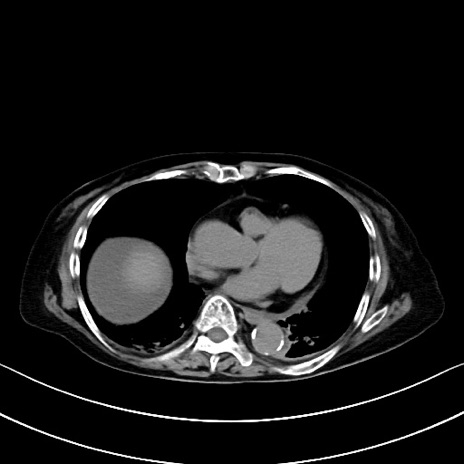

横断像

他院CT